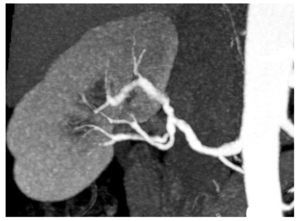

También se valoraron signos sugestivos de enfermedad de tipo displasia fibromuscular, tales como la presencia de arterias renales con estenosis y dilataciones alternantes (fig. 2). Otros tipos de patología con repercusión vascular fueron también tenidos en consideración. Hubo que valorar en este contexto posibles estenosis posquirúgicas en los dos pacientes portadores de trasplante, y también se consideró la hipotética presencia de disecciones arteriales espontáneas. Las displasias fibromusculares y las disecciones espontáneas se valoraron al menos como estenosis de grado II. Las estenosis posquirúgicas se valoraron de forma similar a las de etiología ateromatosa.

Fig. 2. Proyección coronal de tipo máxima intensidad de señal de riñón y arteria renal derecha. Se aprecian las típicas dilataciones y estenosis en "collar de cuentas" de la displasia fibromuscular.